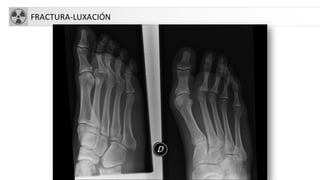

FRACTURA-LUXACIÓN

• Luxación: Pérdida completa de continuidad entre2 extremos óseos.

• Subluxación: pérdida parcialde alineación entre 2 caras articulares.

• Diástasis: Separación delos 2 extremos óseos conservándosela

alineación (sínfisis pubis).